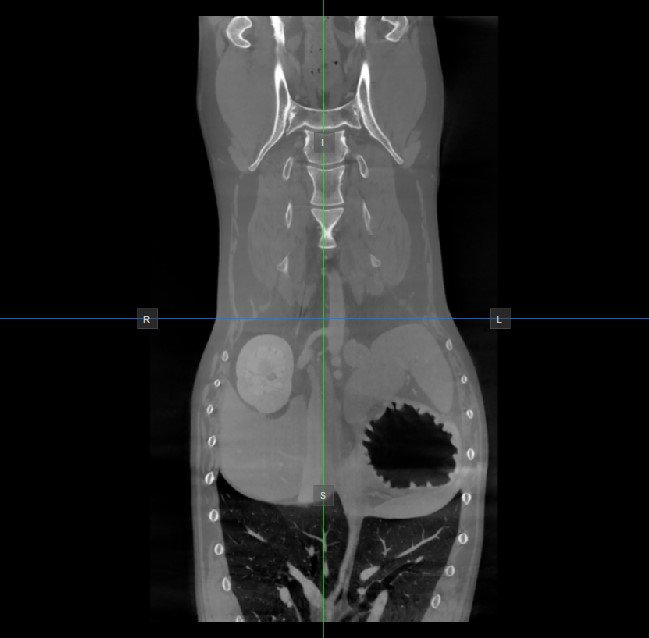

Image Orientation and Image Planes¶

The position and intersection of the other two image planes not represented in the active viewport is indicated by two vertical and horizontal lines called slicers. The endpoints of each slicer are labeled with a letter that corresponds to the appropriate direction/side of the 3D volume, based on the RAS coordinate system.

Only four sides of the available six are indicated on each 2D viewport. The labels and the corresponding side are the following:

Patient Right (R), indicating the right side of the body

Patient Left (L), indicating the left side of the body

Anterior (A), indicating the front side of the body

Posterior (P), indicating the back side of the body

Superior (S), indicating the top side of the body

Inferior (I), indicating the bottom side of the body